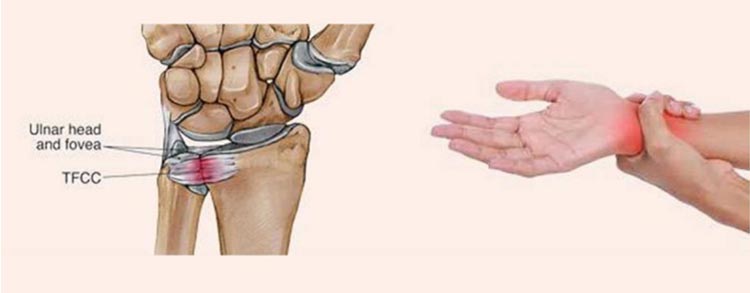

手腕中存在一个组织,叫“三角纤维软骨复合体”(TFCC),它的功能有点类似于膝关节中的半月板。它主要的作用是缓冲腕部受到的力量并增强腕关节的稳定性,一旦它出现损伤,就会出现手腕的顽固性疼痛。

TFCC常见的损伤症状:

(1)活动腕关节后有响声

(2)手腕不能旋转,旋转后疼痛

(3)腕部力量下降

(4)常见动作无法完成,如:拧毛巾,拧门把手,手腕90°撑椅起身等。